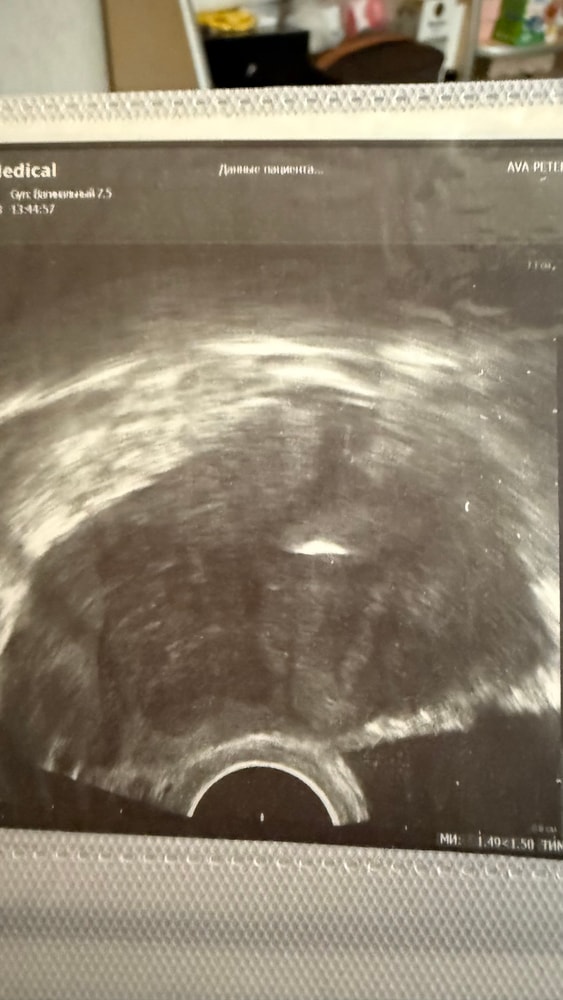

Протоколы ЭКО (Все о них, все об этом периоде+Гиперстимуляция)Девочки могли бы вы приложить в комментариях фото с переноса куда в какое место матки перенесли вам эмбрион в успешном крио? Там есть обычно белая точка это и есть место переноса (точка различимая на узи) у меня есть подозрения что мне перенесли очень низко прям у цервикального канала и эмбрион мог попросту на 1дпп выпасть (были выделения в виде круглых кровяных сгустков)

также меня смущают множество белесых полосок по всей длине в структуре матки и в центре , были ли такие же у вас такие ? Очень обеспокоена поделитесь пожалуйста

Вот мой перенесенный который уже родился